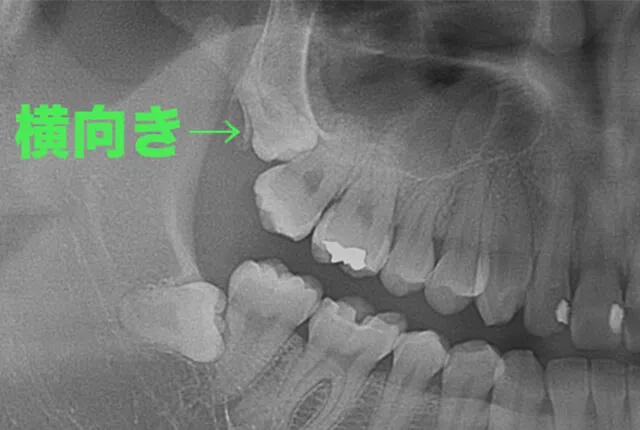

下顎の横向き親知らず

下顎の横向きの親知らずは、抜歯の難易度が高くなります。これは、親知らずが手前の7番にぶつかっているため、そのままでは抜けないからです。

この場合、歯を削る機械を使って親知らずの頭と根を分割し、頭の部分を先に取り出してから、残った根を抜いていきます。分割の回数は歯の状態によって異なり、1回で済む場合もあれば、3〜4分割が必要な場合もあります。

上顎の横向き親知らず

上顎の親知らずでも、まれに横向きに生えている場合があります。下顎の横向き親知らずほど頻繁には見られませんが、まっすぐな親知らずよりも外科的難易度は高くなります。